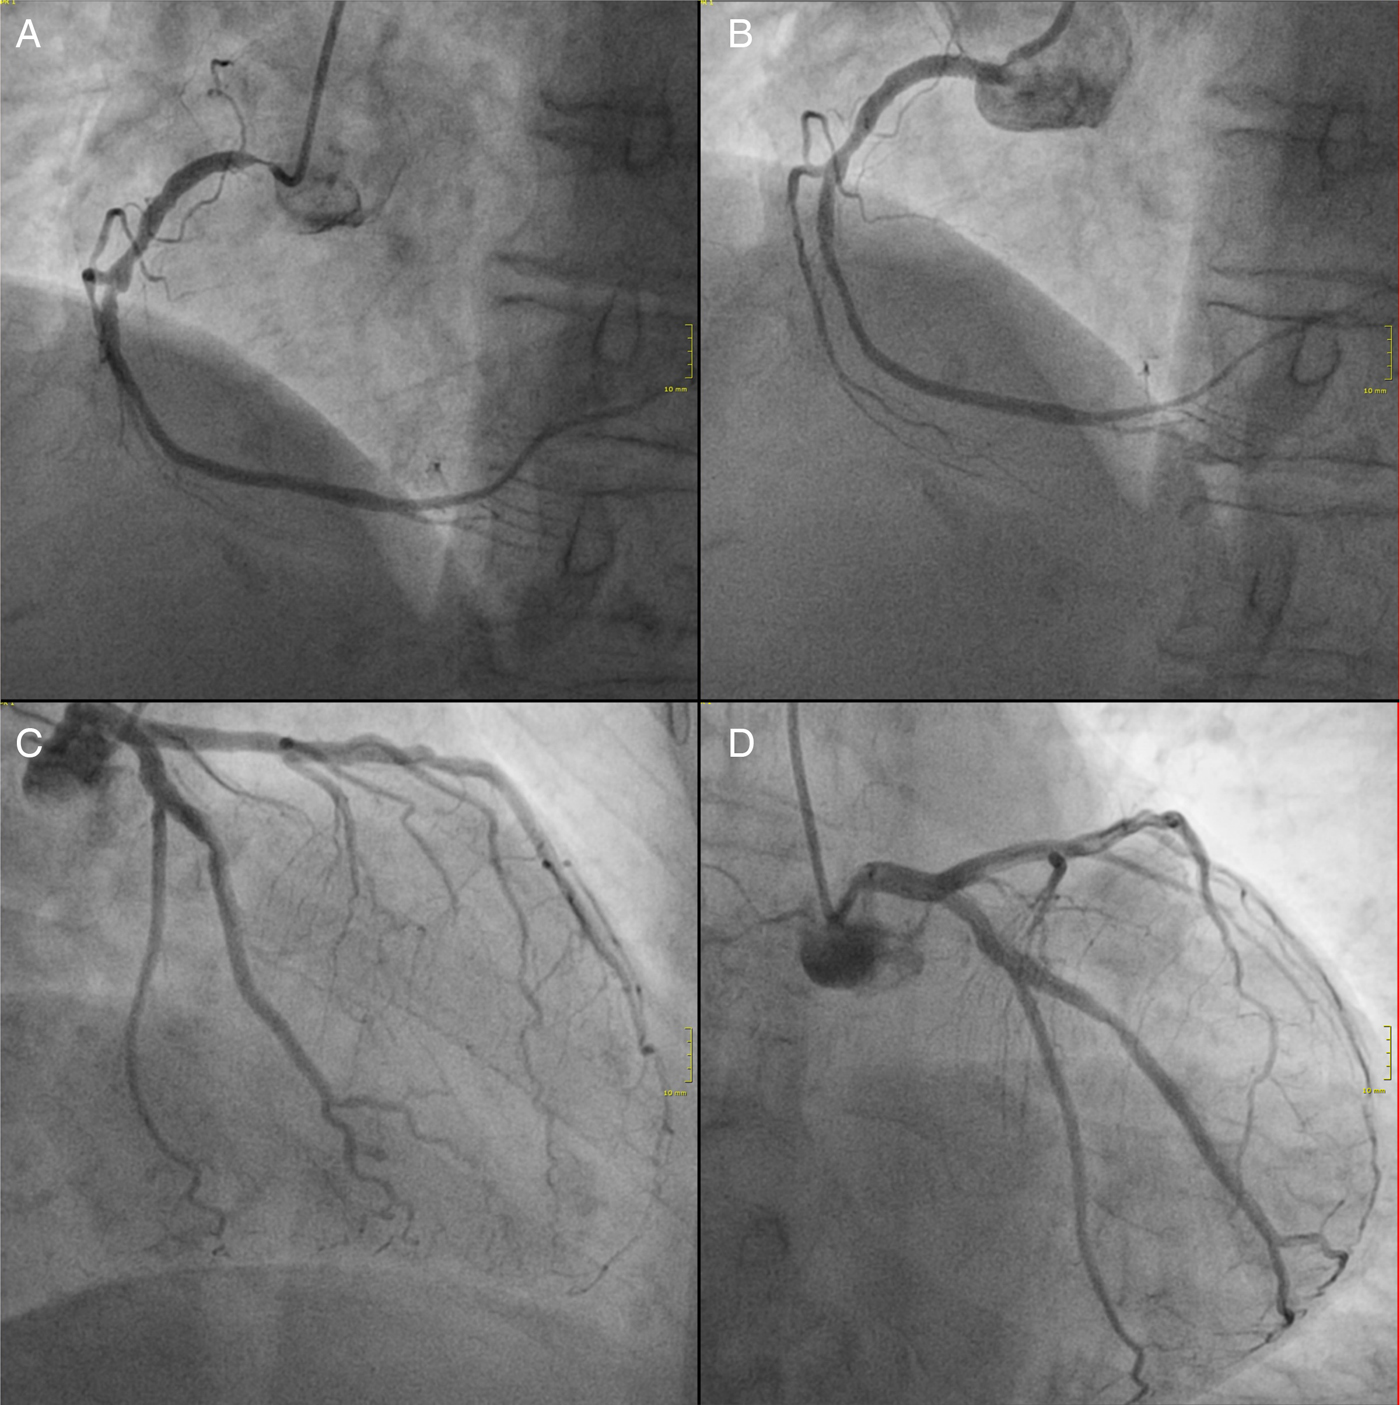

An 86-year-old woman was admitted because of her first syncopal episode, without further symptoms. ECG at admission showed a high-degree AV block with a stable escape rhythm of 50 beats per minute, narrow QRS complexes, an isolated ST elevation in lead III, and an incomplete right bundle branch block (Figure 1). Echocardiography did not reveal any localized wall motion abnormalities and excluded valvular heart disease. There was no history of diabetes mellitus, and the glucose level at admission was within a normal range. Because of hypertension, the patient was on chronic treatment with a beta-blocker, an angiotensin II receptor antagonist, hydrochlorothiazide, and an aldosterone antagonist. The first blood test was unremarkable; the initial high-sensitive cardiac troponin I (hsTNI) level (Abbott ARCHITECT STAT high-sensitive troponin I immunoassay, Wiesbaden, Germany) was negative (7 pg/ml). The patient was scheduled for a pacemaker implantation. A second blood test of biomarkers three hours later showed a marked elevation of hsTNI (25,290 pg/ml). Immediate cardiac catheterization was performed revealing subtotal ostial stenosis of the right coronary artery (Figure 2A). The left coronary artery had no significant stenosis (Figure 2B and 2C). Stent implantation was performed successfully (Figure 2D). During the hospital stay, the patient remained asymptomatic, and the AV block disappeared (Figure 3). Five days later the patient could be discharged without further sequelae.

Figure 2. Coronary angiography. (A) Subtotal ostial occlusion of the right coronary artery (40°/0° projection). (B) Right coronary artery after successful ostial stent deployment. (C and D) Left coronary artery without significant stenosis in two projections (C in −30/0° projection; D in 0°/−30° projection).